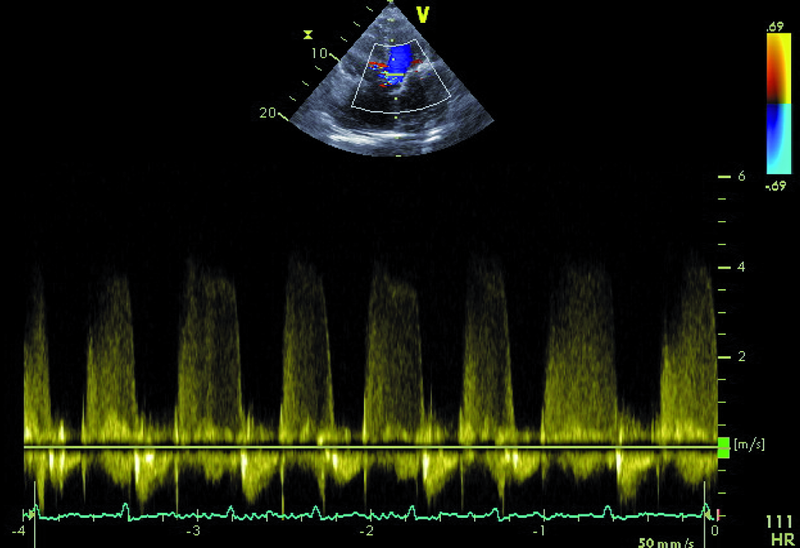

Kobieta, lat 73. Jakie patologie można rozpoznać na rycinach?

1. Ubytek przegrody międzyprzedsionkowej typu II (ryc. 1).

2. Niedomykalność zastawki trójdzielnej (ryc. 1).